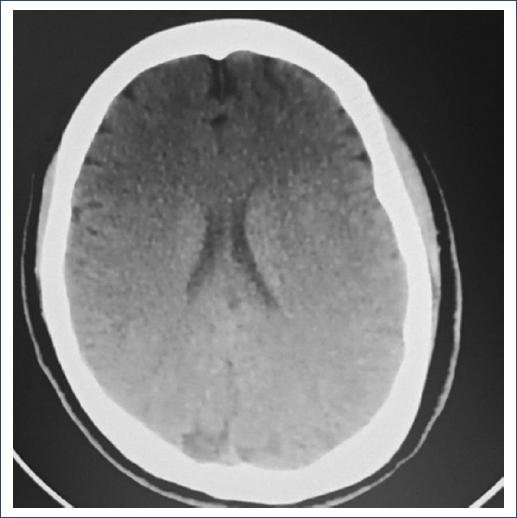

GCS 12 points: bilateral pupillary diameter 2 mm, brainstem reflexes and no cranial nerve alterations, unaltered motor sensitivity and response, and altered mental functions. Grade III osteotendinous reflexes. She underwent neurocritical care on the recommendation of the neurology service, remained under deep sedation after cesarean section for 48 h, with ICP monitoring inferred by optic nerve sheaths diameter measurement ICP 10-12 mmHg, and subsequently emerged without data of delirium, without any manifestation of neurological deterioration. Tomography: Density changes compatible with thrombosis of the superior longitudinal sinus, without any other alteration at the intraparenchymal or ventricular level (Fig. 4).

SUMMARY OF CLINICAL EVOLUTION